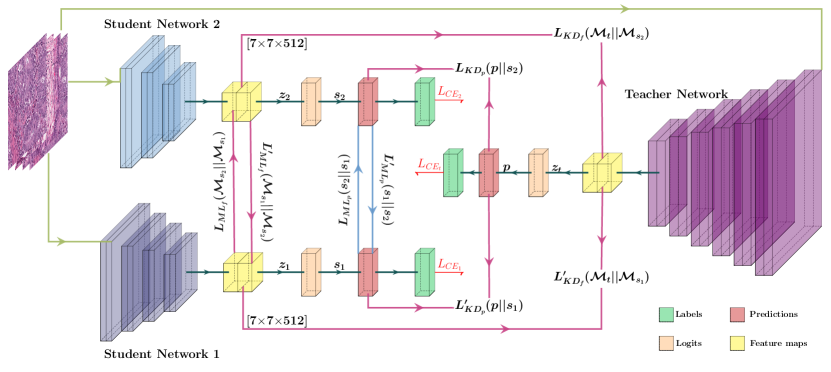

In our approach, which uses a combined KD + ML configuration with a knowledge diversification strategy to distill knowledge from the teacher while facilitating mutual learning among students, we define the respective loss functions as follows:

| (6) |

| (7) |

where and represent the same loss terms based on predictions as defined in equations 4 and 5 respectively. To encourage knowledge diversification, we introduce two supplementary loss terms, and . These loss terms are constructed based on features shared by the teacher, represented as , and the other student, denoted as . We define the feature map-based loss function as the Mean Square Error (MSE) between the feature maps of the corresponding networks. In general, for n number of feature maps, the MSE between two feature maps is defined as . The detailed depiction of our proposed approach with a knowledge diversification strategy is shown in Figure 3, and the network architecture details are given in Table 6 in the supplementary material. Refer to Table 5 (supplementary material) for a comprehensive view of the different loss terms involved in the distillation methods with various learning styles.

Using Equations 6 and 7, we can derive the loss functions for KD-only and ML-only configurations with knowledge diversification by setting weighing parameters and respectively. As each student is learning from different information, we use separate weighing parameters for individual terms of the loss function and optimize them using grid search. For a test sample , we consider the ensemble classification probability, , as the highest probability for a particular class across all student network predictions. This is given as .

Although sharing predictions is a common practice, a more detailed explanation is required for the sharing of feature information. With the assumption that the last layers of deep neural networks encode high-level semantic information, we propose to use the output of the teacher network’s last convolution layer as feature information to share with student networks. However, to enable this knowledge transfer, it is necessary to ensure that the student network’s convolutional block has an output feature map with dimensions matching the teacher network’s. This ensures an effective transfer of knowledge between the two networks. In KD configurations, where the teacher and student networks do not have layers with matching dimensions to share or compare the feature map information, an additional convolutional block can be added to the teacher network with an output dimension to match that of the student. This ensures the compactness of the student networks. A similar approach can also be adopted for ML configurations with non-identical student networks.